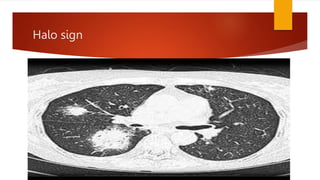

 the presence of a ‘halo sign’ (a zone of

intermediate attenuation between the nodule and

the lung parenchyma) may suggest aspergillosis

Cont..  the presenceof a ‘halo sign’ (a zone of intermediate attenuation between the nodule and the lung parenchyma) may suggest aspergillosis  pleural effusions suggest pyogenic bacterial infections and are uncommon in P. jirovecii pneumonia